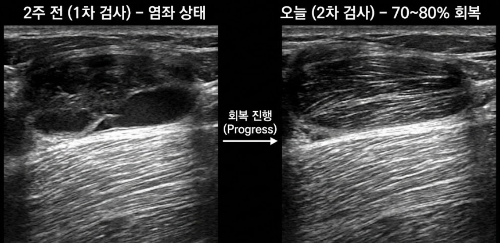

오늘은 두 번째 초음파 검사를 받은 날입니다.

2주 전, 처음 초음파를 봤을 때 화면 속 제 우측 허벅지는 꽤 충격적이었습니다.

아래쪽 근육은 정상인데, 위쪽은 검게 비어 있는 듯한 염좌 소견.

의사 선생님께서는 “근육 섬유가 찢어지고 염증과 출혈이 섞인 상태”라고 설명해 주셨습니다.

초음파 화면에는 확연한 변화가 있었습니다.

예전에는 까맣게 보이던 손상 부위 위로

하얀 가로 근육 실줄들이 다시 나타났습니다.

의사 선생님 표현으로는 “70~80% 정도 회복”.

근육 조직이 다시 살아나며 섬유들이 재정렬되고 있다는 뜻이었습니다.